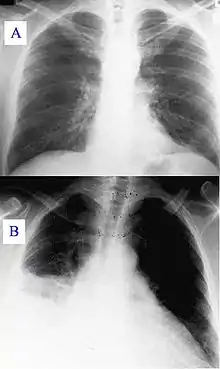

Основными методами диагностики являются рентгенологическое исследование лёгких и исследование мокроты, основным методом лечения — антибактериальная терапия. Поздняя диагностика и задержка с началом антибактериальной терапии ухудшают прогноз заболевания. В некоторых случаях возможен смертельный исход.

Диагностические методы исследования

- Рентгенография грудной клетки